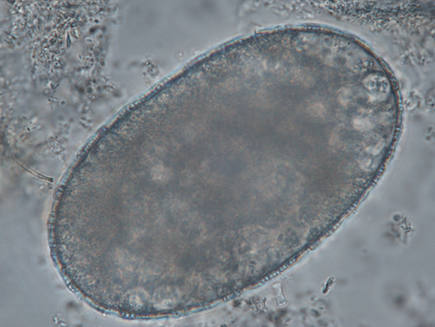

Trematode eggs are large, ranging from 130 to 140 µm long and 80 to 85 µm large, and are operculated. Their content is granulomatous. It is impossible to differentiate the species of trematodes using ovodiagnosis (Garcia, 2021).

Differential diagnosis includes mite eggs, which are of the same size approximately. In their immature states, they contain nutritive granules which could induce confusion with trematode eggs. However, they are normally more heterogeneous, with the center being darker than the periphery of the egg. In their mature form, mite embryos are clearly visible, and no confusion can be made (Petithory et al., 1995).